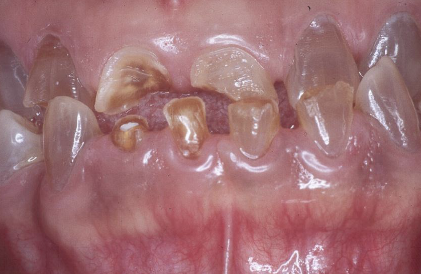

a hereditary condition of dentin in the absence of any systemic disease (opalescent dentin), AD, genetic mutation is DIFFERENT from osteogenesis imperfecta

dentinogenesis imperfects (DGI)

DGI-II clinical presentation

isolated opalescent teeth, most common

affects both dentition, steel-grey/ translucent/ opalescent crowns, brittle enamel

DGI

DGI radiographic presentation

bulbous crown, cervical constriction, pulp obliteration varies, expanded pulp = shell teeth